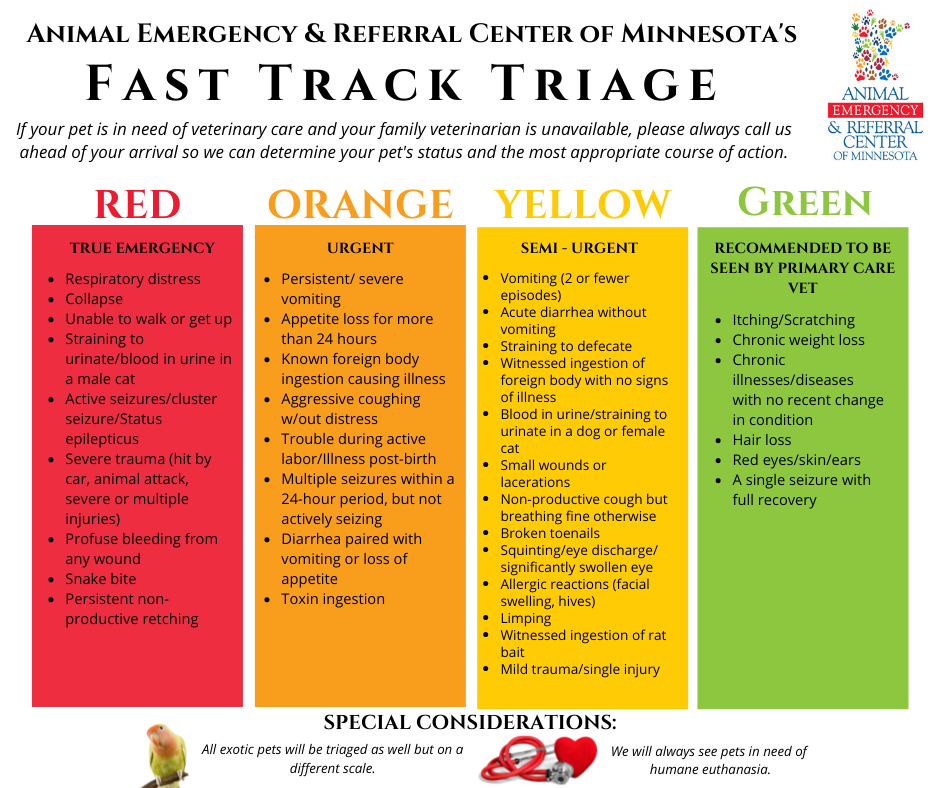

If your pet is experiencing persistent, non-productive retching, this is considered a “RED” – or true emergency – on our Fast Track Triage chart. We advise you to seek immediate veterinary care. Please call ahead of your arrival so the veterinary team knows to expect you!

- Non-productive retching & a painful, enlarged stomach are signs of Gastric Dilatation and Volvulus (GDV), also known as “bloat”, “twisted stomach”, or “flipped stomach.”